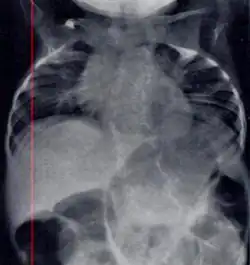

| Radiograph depicting typical skeletal features of Jarcho-Levin syndrome, subtype spondylothoracic dysplasia. Note fanlike configuration of the ribs, with extensive posterior fusion, along with multiple vertebral segmentation defects. | |

Spondylothoracic dysplasia

Spondylothoracic dysplasia, or STD, has been repeatedly described as an autosomal recessively inherited condition that results in a characteristic fan-like configuration of the ribs with minimal intrinsic rib anomalies. Infants born with this condition typically died early in life due to recurrent respiratory infections and pneumonia due to their restricted thorax.[3][4][5] Recently, a report[6] has documented that actual mortality associated with STD is only about 50%, with many survivors leading healthy, independent lives.

Spondylocostal dysostosis

In contrast to STD, the subtype spondylocostal dysostosis, or SCD features intrinsic rib anomalies, in addition to vertebral anomalies. Intrinsic rib anomalies include defects such as bifurcation, broadening and fusion that are not directly related to the vertebral anomalies (such as in STD, where extensive posterior rib fusion occurs due to segmentation defects and extreme shortening of the thoracic vertebral column).[6] In both subtypes, the pulmonary restriction may result in pulmonary hypertension, and have other potential cardiac implications.[7]